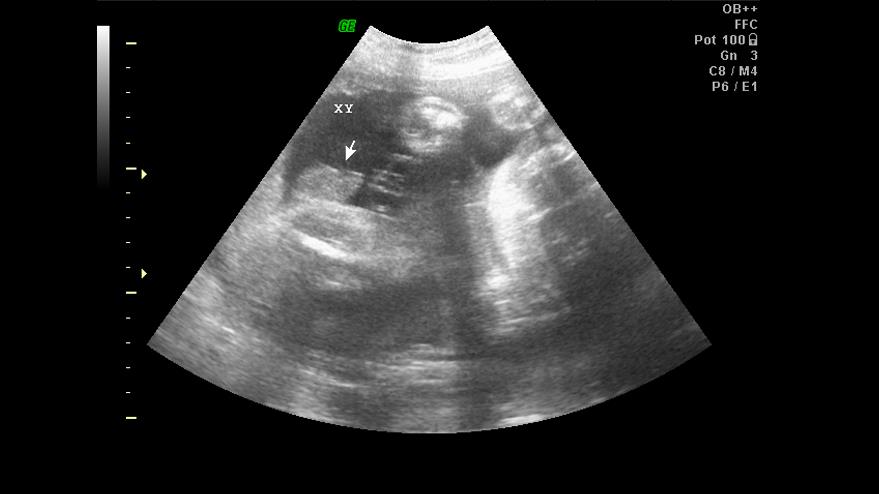

Los investigadores han hallado un mecanismo particular que puede 'desactivar' este virus en un embrión temprano al agregar un enlace de metilo a la adenina, exactamente en el cromosoma X, que es el que determina el sexo, según informa la revista Nature.

Así, esos cromosomas se mantienen activos si el nivel de este marcador molecular es normal —hembras y machos nacen en la misma proporción— y se inactivan si el marcador está excesivamente representado, con lo cual hay una proporción 2 a 1 entre machos y hembras.